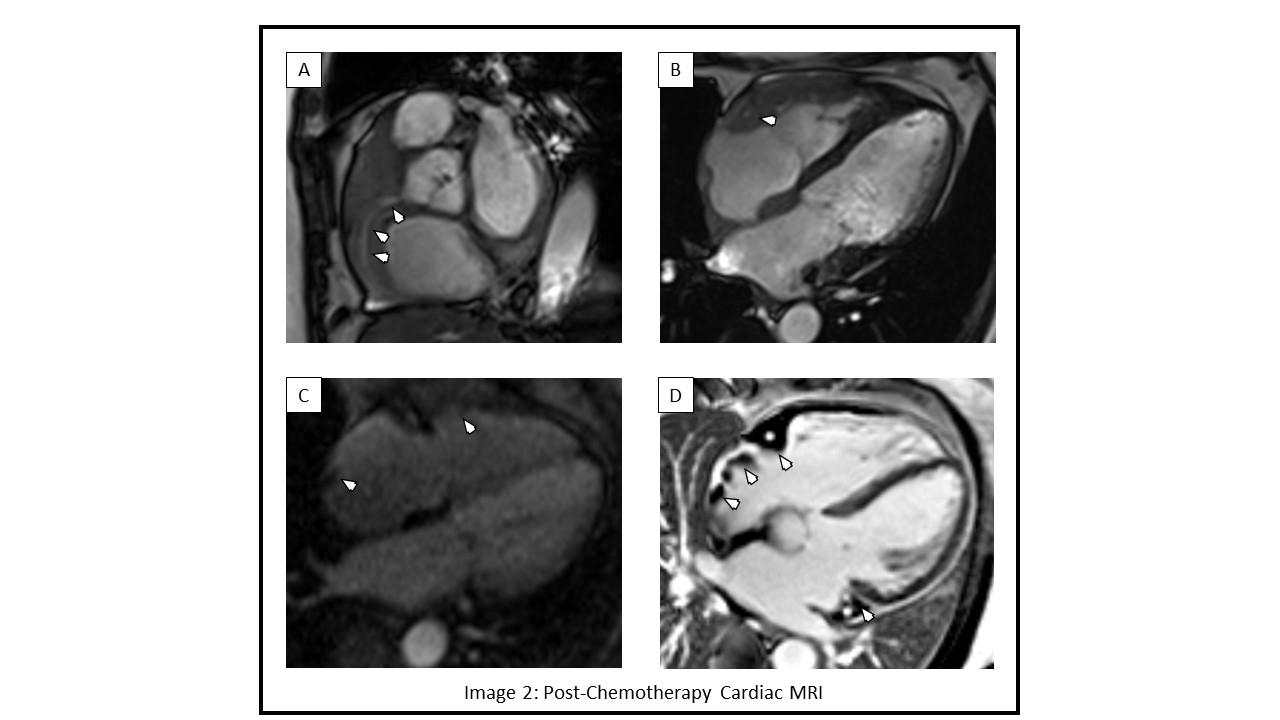

Traditionally, DLBCL is treated with R-CHOP (Rituximab, Cyclophosphamide, Doxorubicin, Vincristine, Prednisone), however up to 40% of patients develop refractory disease or have a relapse1. As in the recent POLARIX trial1, our patient underwent three cycles of novel regimen of Pola-R-CHP. Follow up PET showed dramatic response with metabolic remission (Image 3). Cardiac MRI showed reduction in RV tumor, RA thrombus and inflammatory burden with preserved LV and RV function (Image 2). No further arrhythmias were noted and the patient completed chemotherapy. This case highlights a positive outcome in a patient with aggressive DLBCL with cardiac metastasis treated with Polatuzumab based therapy.